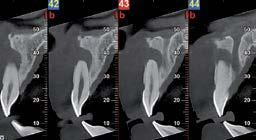

Nell’ambito della radiologia 3D ortopedica, il centro diagnostico utilizza il nuovissimo macchinario NewTom 5G XL, in grado di individuare con la massima precisione la presenza di fratture o lussazioni delle articolazioni, controllare la corretta guarigione di una frattura, valutare una lesione o una ferita causata da infezione, artrite o crescita anormale dell’osso.

Il tutto mediante una semplice e veloce scansione, grazie alla quale si otterranno diverse immagini in 3D ad altissima risoluzione e, per ottenere immagini ancora più nitide mediante un bassissimo dosaggio di radiazioni, gli esperti si avvalgono dell’innovazione racchiusa nella tecnologia Cone Beam.

Se con la radiologia tradizionale era necessario eseguire scansioni multiple, la novità introdotta dal macchinario NewTom 5G XL risiede nella capacità di fornire immagini ad alta risoluzione in un’unica scansione, mostrando nitidamente i dettagli delle articolazioni degli arti superiori e inferiori. Inoltre, a differenza della tecnologia 2D, la radiologia 3D ortopedica permette di individuare immediatamente alcune patologie come quella del metatarso, la quale richiede un allineamento visivo dedicato o una diagnosi delle micro fratture ossee.